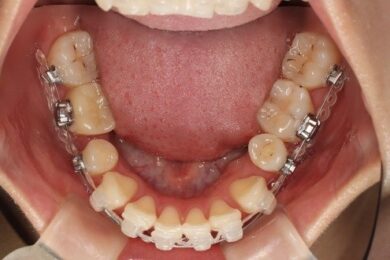

下顎のビフォアアフター

2か月前 現在

下顎の方は重なりが解けるよう、一本一本並ぶように全体的に動いてきています。

臼歯の内側に倒れていたところも起きてきて上を向くようになってきています。

今までは抜歯したところを中心にパワーチェーンをつけていましたが、今回の調整からはパワーチェーンを全体につけ奥(後ろ)に下げていきます。全体の重なりをなくしていきます。